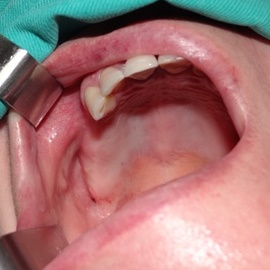

Po utracie zęba w przednim odcinku łuku zębowego należy zwrócić wzmożoną uwagę na aspekt estetyczny. Naczelnym przesłaniem odbudowy brakujących tkanek (anatomiczno-funkcjonalny kompleks tkanek: kość wyrostka zębodołowego + dziąsło + zęby) jest uzyskanie takiego wyniku, który jest najbliżej ideału, czyli takiej sytuacji jak gdyby nic się nie stało i w ogóle nie doszło do utraty zęba i tkanek około zębowych. Kluczem do sukcesu jest odtworzenie poprawnych stosunków anatomicznych: kość - dziąsło - ząb.

Korona protetyczna na implancie, funkcjonująca od roku 2003. Zdarzył się wypadek motocyklowy. Widzimy klucz do osiągnięcia sukcesu: mikrochirurgia i poprawna anatomiczna odbudowa tkanek. Tego nie zastąpi nawet najdroższy implant!

Pokazano etapową odbudowę brakujących tkanek, wraz z odbudową objętości i kształtu dziąsła.

Odbudowa tkanek i zębów przy wysokiej linii uśmiechu. Zadowalający wynik estetyczny.

Odbudowa brakującej kości, odbudowa anatomicznych stosunków dziąsła i korona całoceramiczna osadzona na łączniku cyrkonowym.